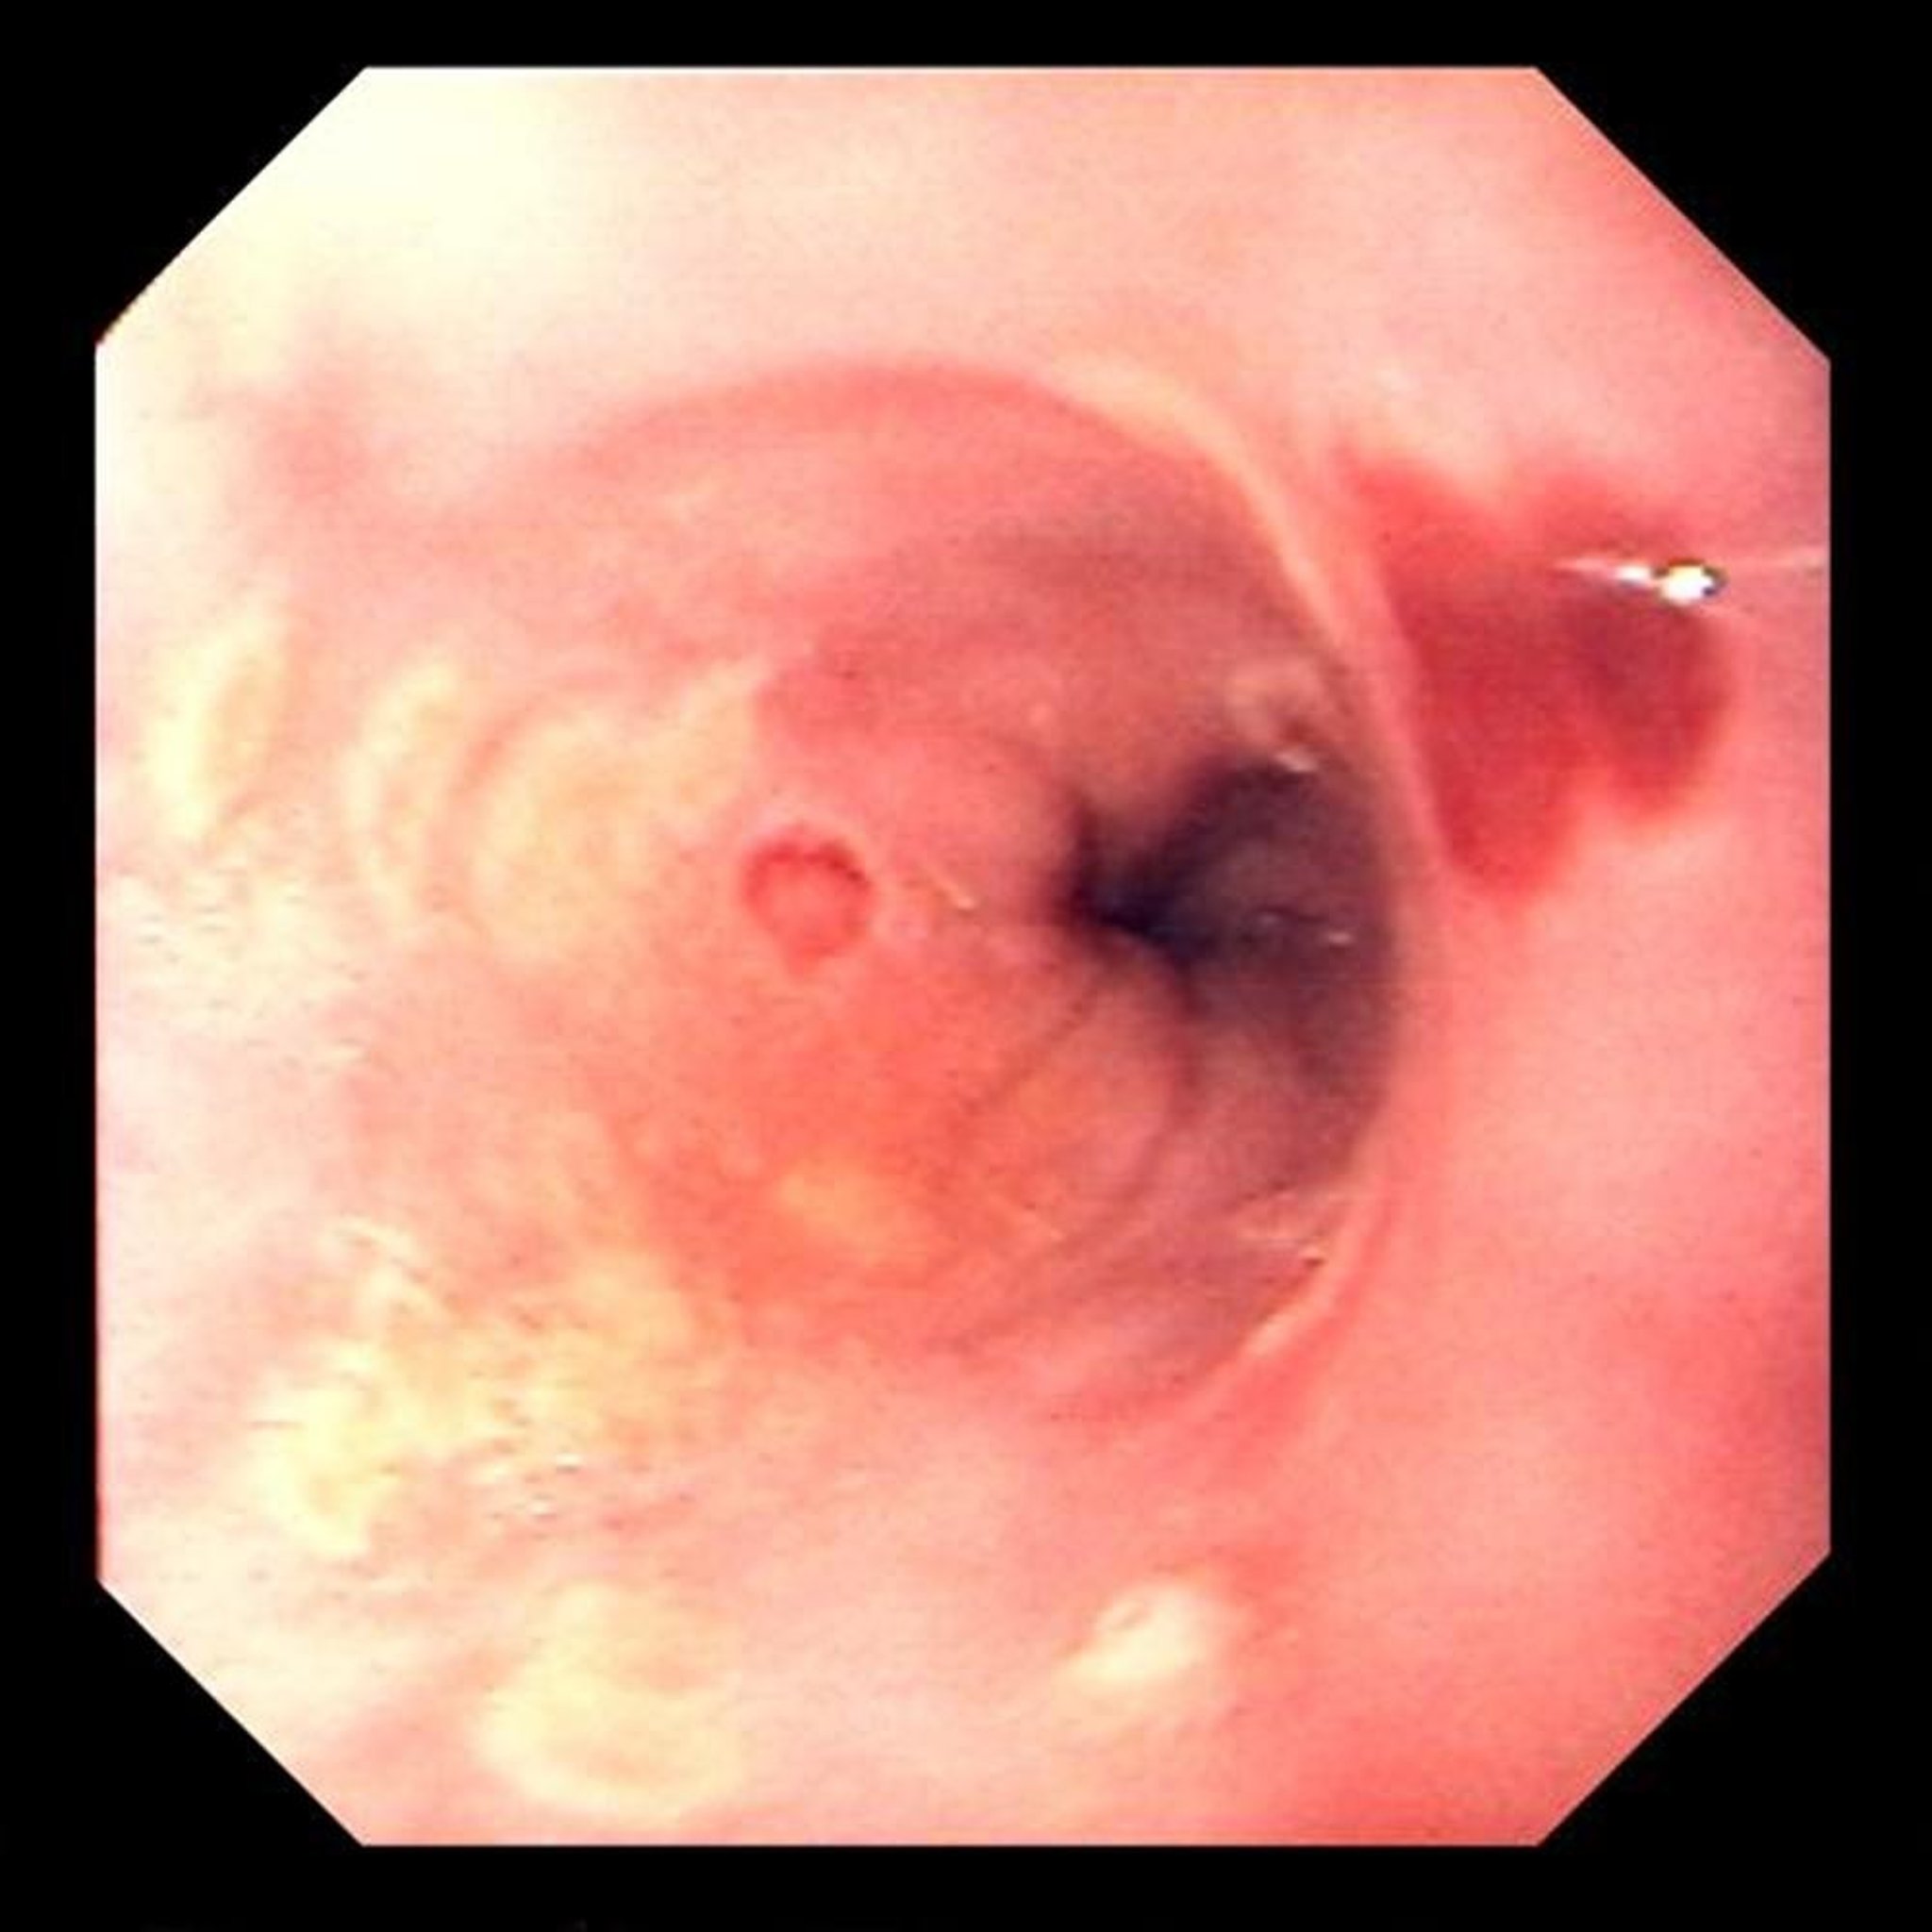

Herpes Simplex Esophagitis

Focal ulcerations are typical of herpes simplex virus esophagitis.

Image provided by David M. Martin, MD.